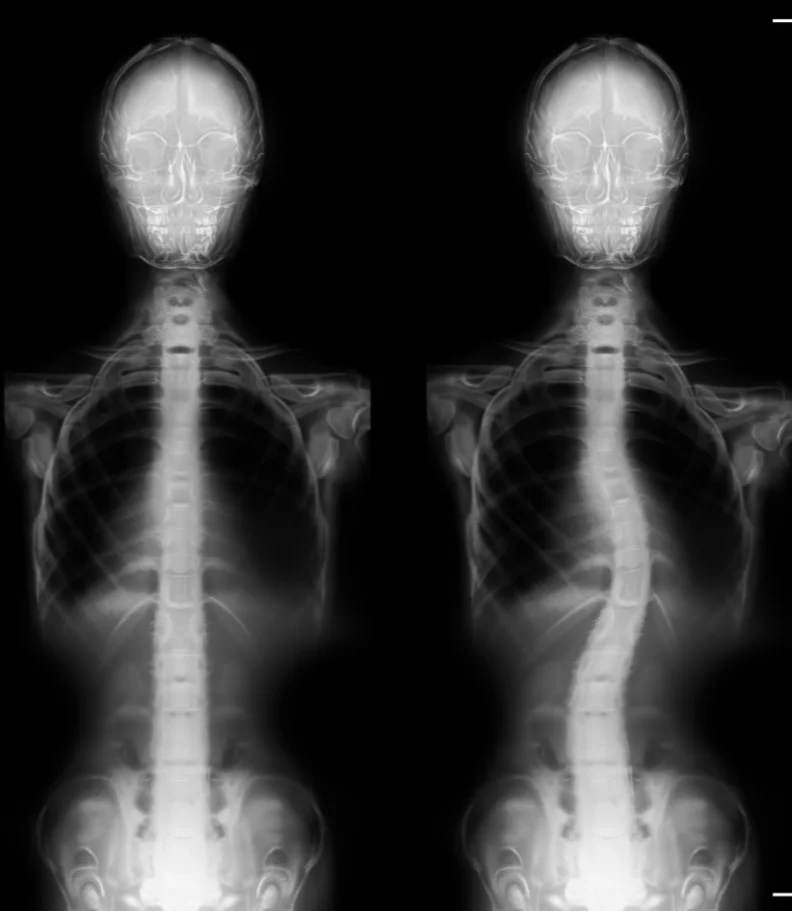

Are you in search of the finest chiropractor in Jefferson City or California, dedicated to caring for scoliosis? Typically, scoliosis begins as a subtle curvature in the spine that gradually intensifies over time. A scoliosis diagnosis occurs when the spine deviates more than ten degrees to either the right or left when facing a medical examiner. As scoliosis advances to more severe stages, it can bring about significant health consequences.

Scoliosis manifests as an abnormal bend or curve in the spine, deviating from the ideal vertical alignment of a healthy spine. The exact origin of this curve can often be elusive. In its early stages, it may begin as a minor bend due to a single vertebra's misalignment. Over time, the body compensates by developing musculature that continues to pull the spine into lateral curves to maintain a level head position.

Often, parents or close associates are the first to notice scoliosis, as the shoulders and pelvis no longer appear level. A thorough physical examination assesses gait and utilizes visual and manual evaluations to determine the extent of spinal curvature. An Adams Position Test, involving the patient bending forward as far as possible, can reveal the presence of an issue. If a noticeable curvature is detected, an X-ray will be employed to assess the severity of scoliosis.